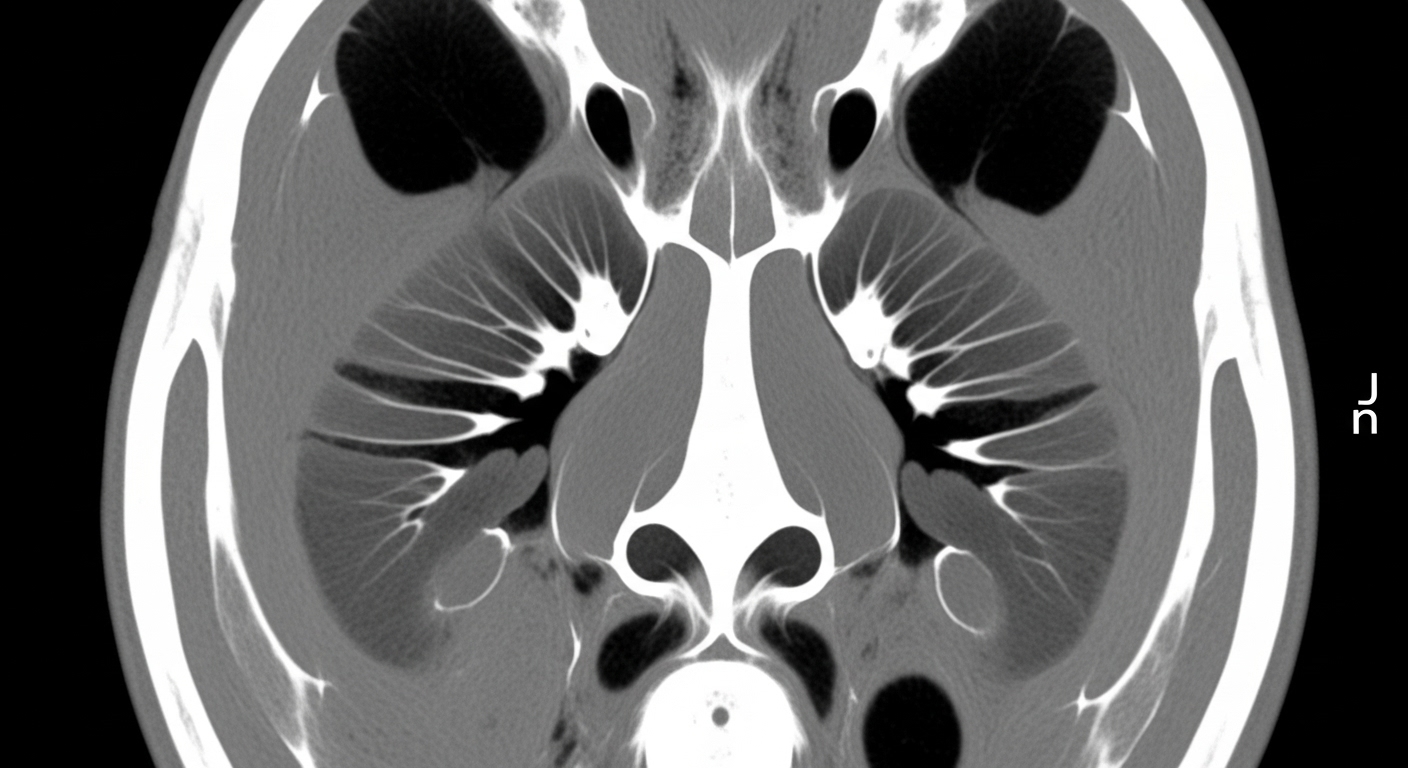

- 전산화단층촬영(CT): 종양의 크기, 위치, 침범 범위

부비동 CT 이미지 (의료 자료)